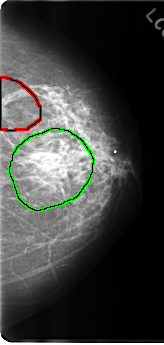

FILE: C_0191_1.LEFT_MLO.OVERLAY

TOTAL_ABNORMALITIES 2

ABNORMALITY 1

LESION_TYPE MASS SHAPE IRREGULAR MARGINS SPICULATED

ASSESSMENT 5

SUBTLETY 5

PATHOLOGY MALIGNANT

TOTAL_OUTLINES 1

ABNORMALITY 2

LESION_TYPE MASS SHAPE IRREGULAR MARGINS ILL_DEFINED